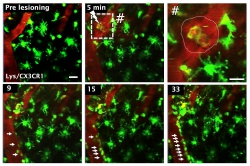

Um pathophysiologische Zusammenhänge und Schlaganfallursachen zu verstehen, werden wissenschaftliche Fragestellung anhand eines umfassenden Schlaganfallregisters seit 2008 untersucht. Insbesondere mit einer leistungsstarken neurovaskulären Spezialambulanz und einer historisch engen Zusammenarbeit mit der Gefäßchirurgie stellen und beantworten wir Fragen zu arteriosklerotischen Veränderungen der hirnzuführenden extra- und intrakraniellen Gefäße. Zudem partizipieren wir an nationalen und internationalen Studien, die zum einen die Akutbehandlung nach Schlaganfall und zum anderen das Verhindern neuer Schlaganfälle, im Sinne einer medikamentösen Sekundärprävention adressieren. Darüber hinaus fokussieren wir in tierexperimentellen Ansätzen, die Rolle des Immunsystems nach einem Schlaganfall zu verstehen und nutzen dabei die intravitale Mikroskopie um dynamisch das Verhalten von Immunzellen zu entschlüsseln (Abbildung 4).